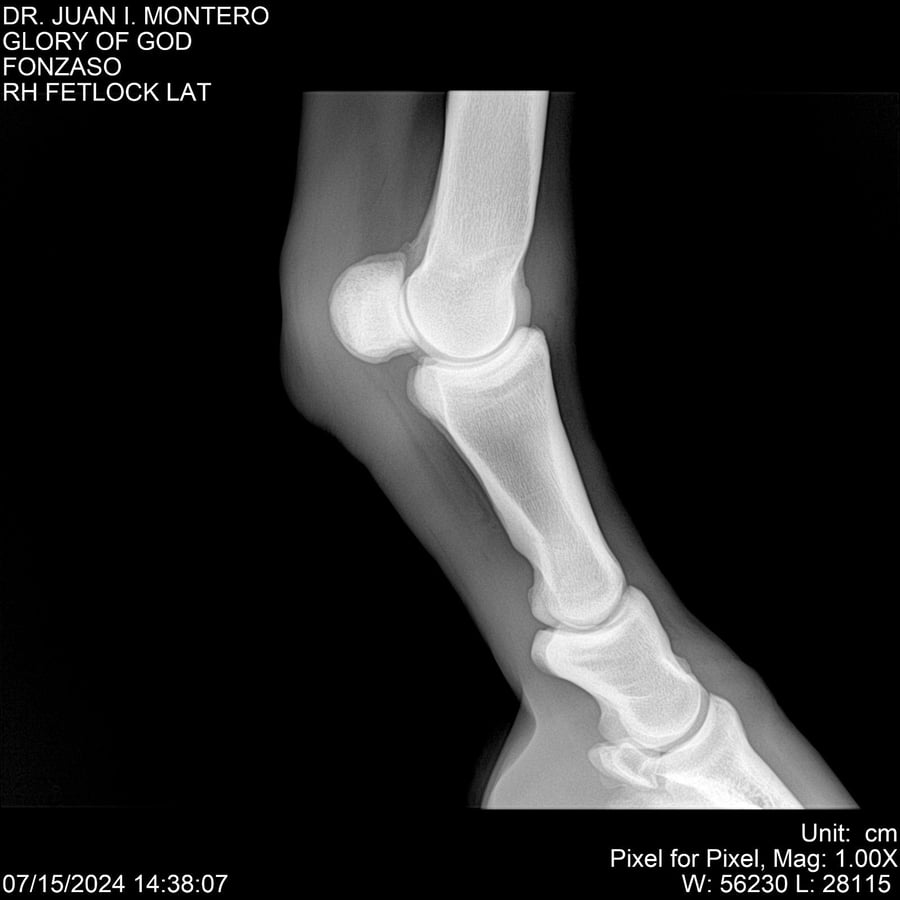

LOTE 10, GLORY OF GOD 🔥 🔥 🔥 Lote Anterior Volver al remate Lote Siguiente Ficha Contacto Montevideo - Ficha del Lote Identificador: #281389 Categoría: Yeguarizos Montevideo - 115 Visualizaciones ClicData Contacto Empresa: Abelenda N. R., Walter Hugo Nombre*: Teléfono* : E-mail* : Mensaje Enviar Registrese gratis Este contenido Exclusivo está disponible sólo para usuarios registrados Ingresar